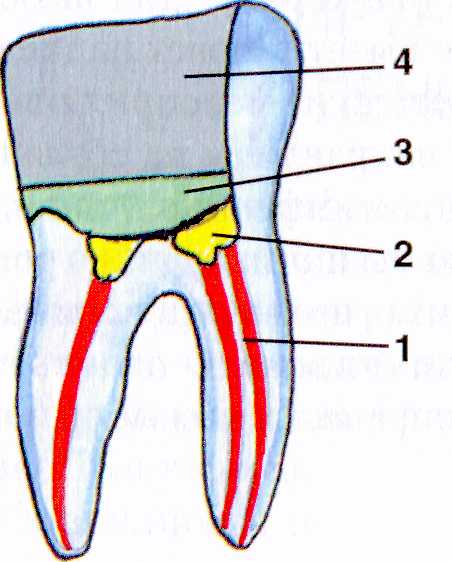

Культя зуба это

Культя зуба это 106 фото